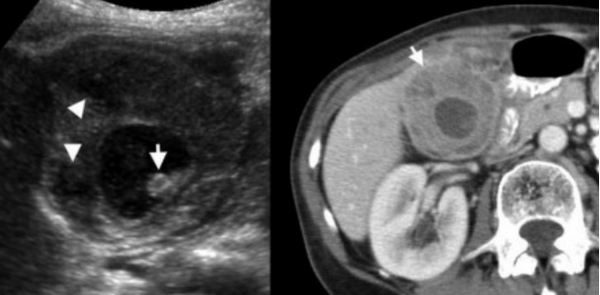

Ксантогранулематозный холецистит.

Ксантогранулематозный холецистит — это воспалительное заболевание, характеризующаяся тем, что в стенке желчного пузыря образуются ксантомы и гранулемы. При исследовании выявляют утолщение стенки желчного пузыря, уменьшение органа в размере, а также интрамуральные узелки, которые визуализируются, как гипоэхогенные включения на УЗИ и гиподенсные на компьютерной томограмме. Данные включения схожи с включениями при карциноме желчного пузыря.

УЗИ и КТ желчного пузыря. Ксантогранулематозный холецистит. Слева на УЗИ визуализируется (помечено стрелками) утолщение стенки желчного пузыря с интрамуральным включением и с камнем в просвете органа. Справа на КТ выявляется утолщение стенки с гиподенсными включениями.

Выше представлено КТ пациента 71 года с ксантогранулематозным холециститом. Постконтрастное КТ. Визуализируется утолщение стенки желчного пузыря с включениями, которые соответствуют абсцессу или фокусам воспаления.